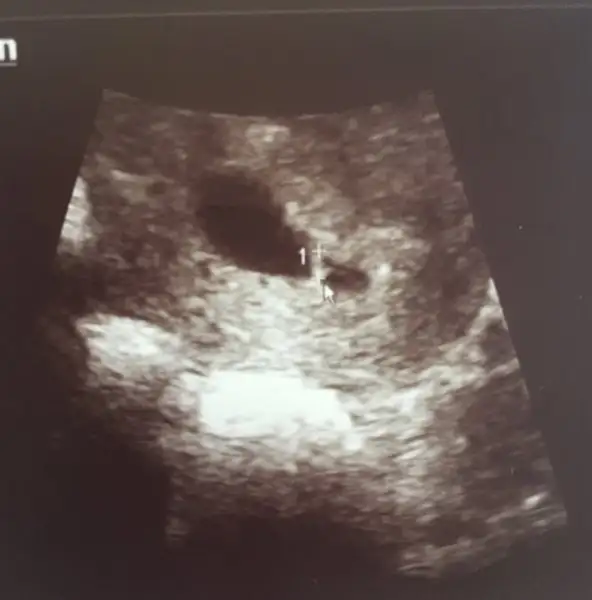

Cinsiyeti ne oldu acaba? Erkek tahmin ettim merakettimilki 6 haftalık diğer ıkısı 9 hafta 4 gün karından sizce nedir

Buraya gelen yok arkadaslar konu ismi veriyorum bebegin konumuna gore cinsiyet belirleme google yazin cikarBizde yorum alabilirmiyiz :)